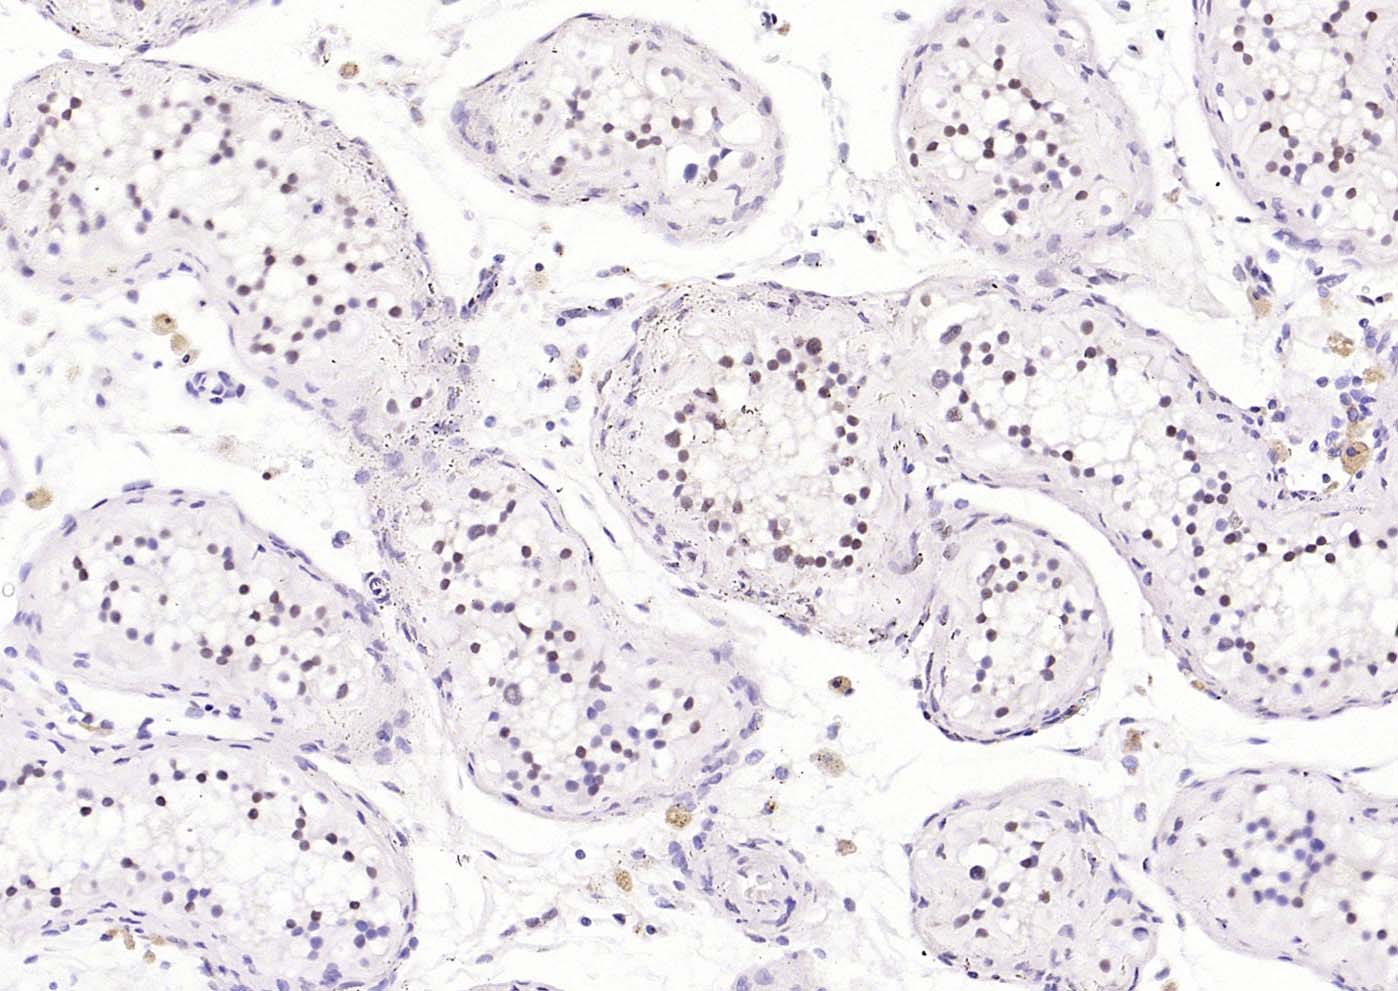

Paraformaldehyde-fixed, paraffin embedded (human testis); Antigen retrieval by boiling in sodium citrate buffer (pH6.0) for 15min; Block endogenous peroxidase by 3% hydrogen peroxide for 20 minutes; Blocking buffer (normal goat serum) at 37°C for 30min; Incubation with (CDCA5) Polyclonal Antibody, Unconjugated (bs-7717R) at 1:200 overnight at 4°C, followed by operating according to SP Kit(Rabbit) (sp-0023) instructionsand DAB staining.

Paraformaldehyde-fixed, paraffin embedded (mouse testis); Antigen retrieval by boiling in sodium citrate buffer (pH6.0) for 15min; Block endogenous peroxidase by 3% hydrogen peroxide for 20 minutes; Blocking buffer (normal goat serum) at 37°C for 30min; Incubation with (CDCA5) Polyclonal Antibody, Unconjugated (bs-7717R) at 1:200 overnight at 4°C, followed by operating according to SP Kit(Rabbit) (sp-0023) instructionsand DAB staining.